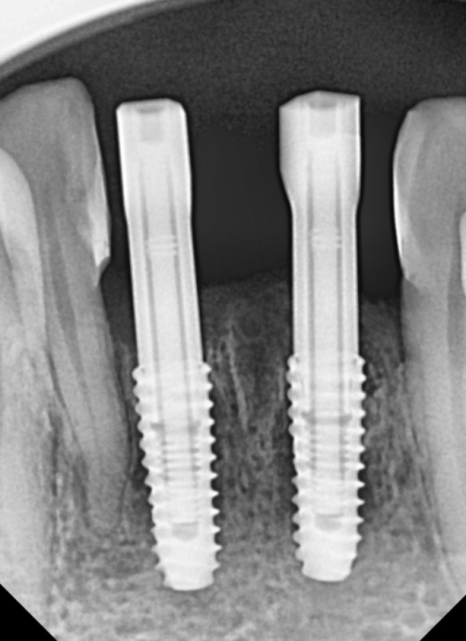

260112

아래쪽 어금니와 앞니 부위도

광범위한 뼈이식과 함께 임플란트를

식립했습니다.